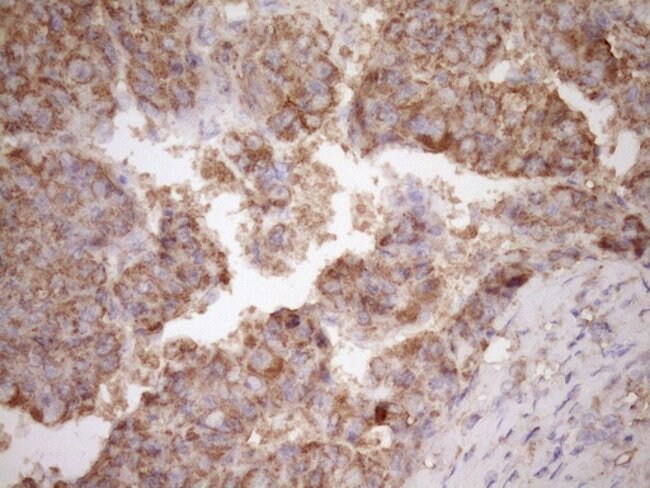

Human fascin is a highly conserved actin-bundling protein. Fascin, encoded by the human homolog for sn (hsn) gene, has been localized to microspikes and stress fibers of cultured cells where it is thought to be involved in the formation of microfilament bundles. It is expressed predomitly in dendritic cells. Lymphoid cells, myeloid cells and plasma cells are negative. However. Reed Sternberg cells in Hodgkin′s lymphoma are positive for fascin staining. Epstein-Barr virus may induce expression of fascin in B cells.Specifications

| Immunohistochemistry (Paraffin), Western Blot | |